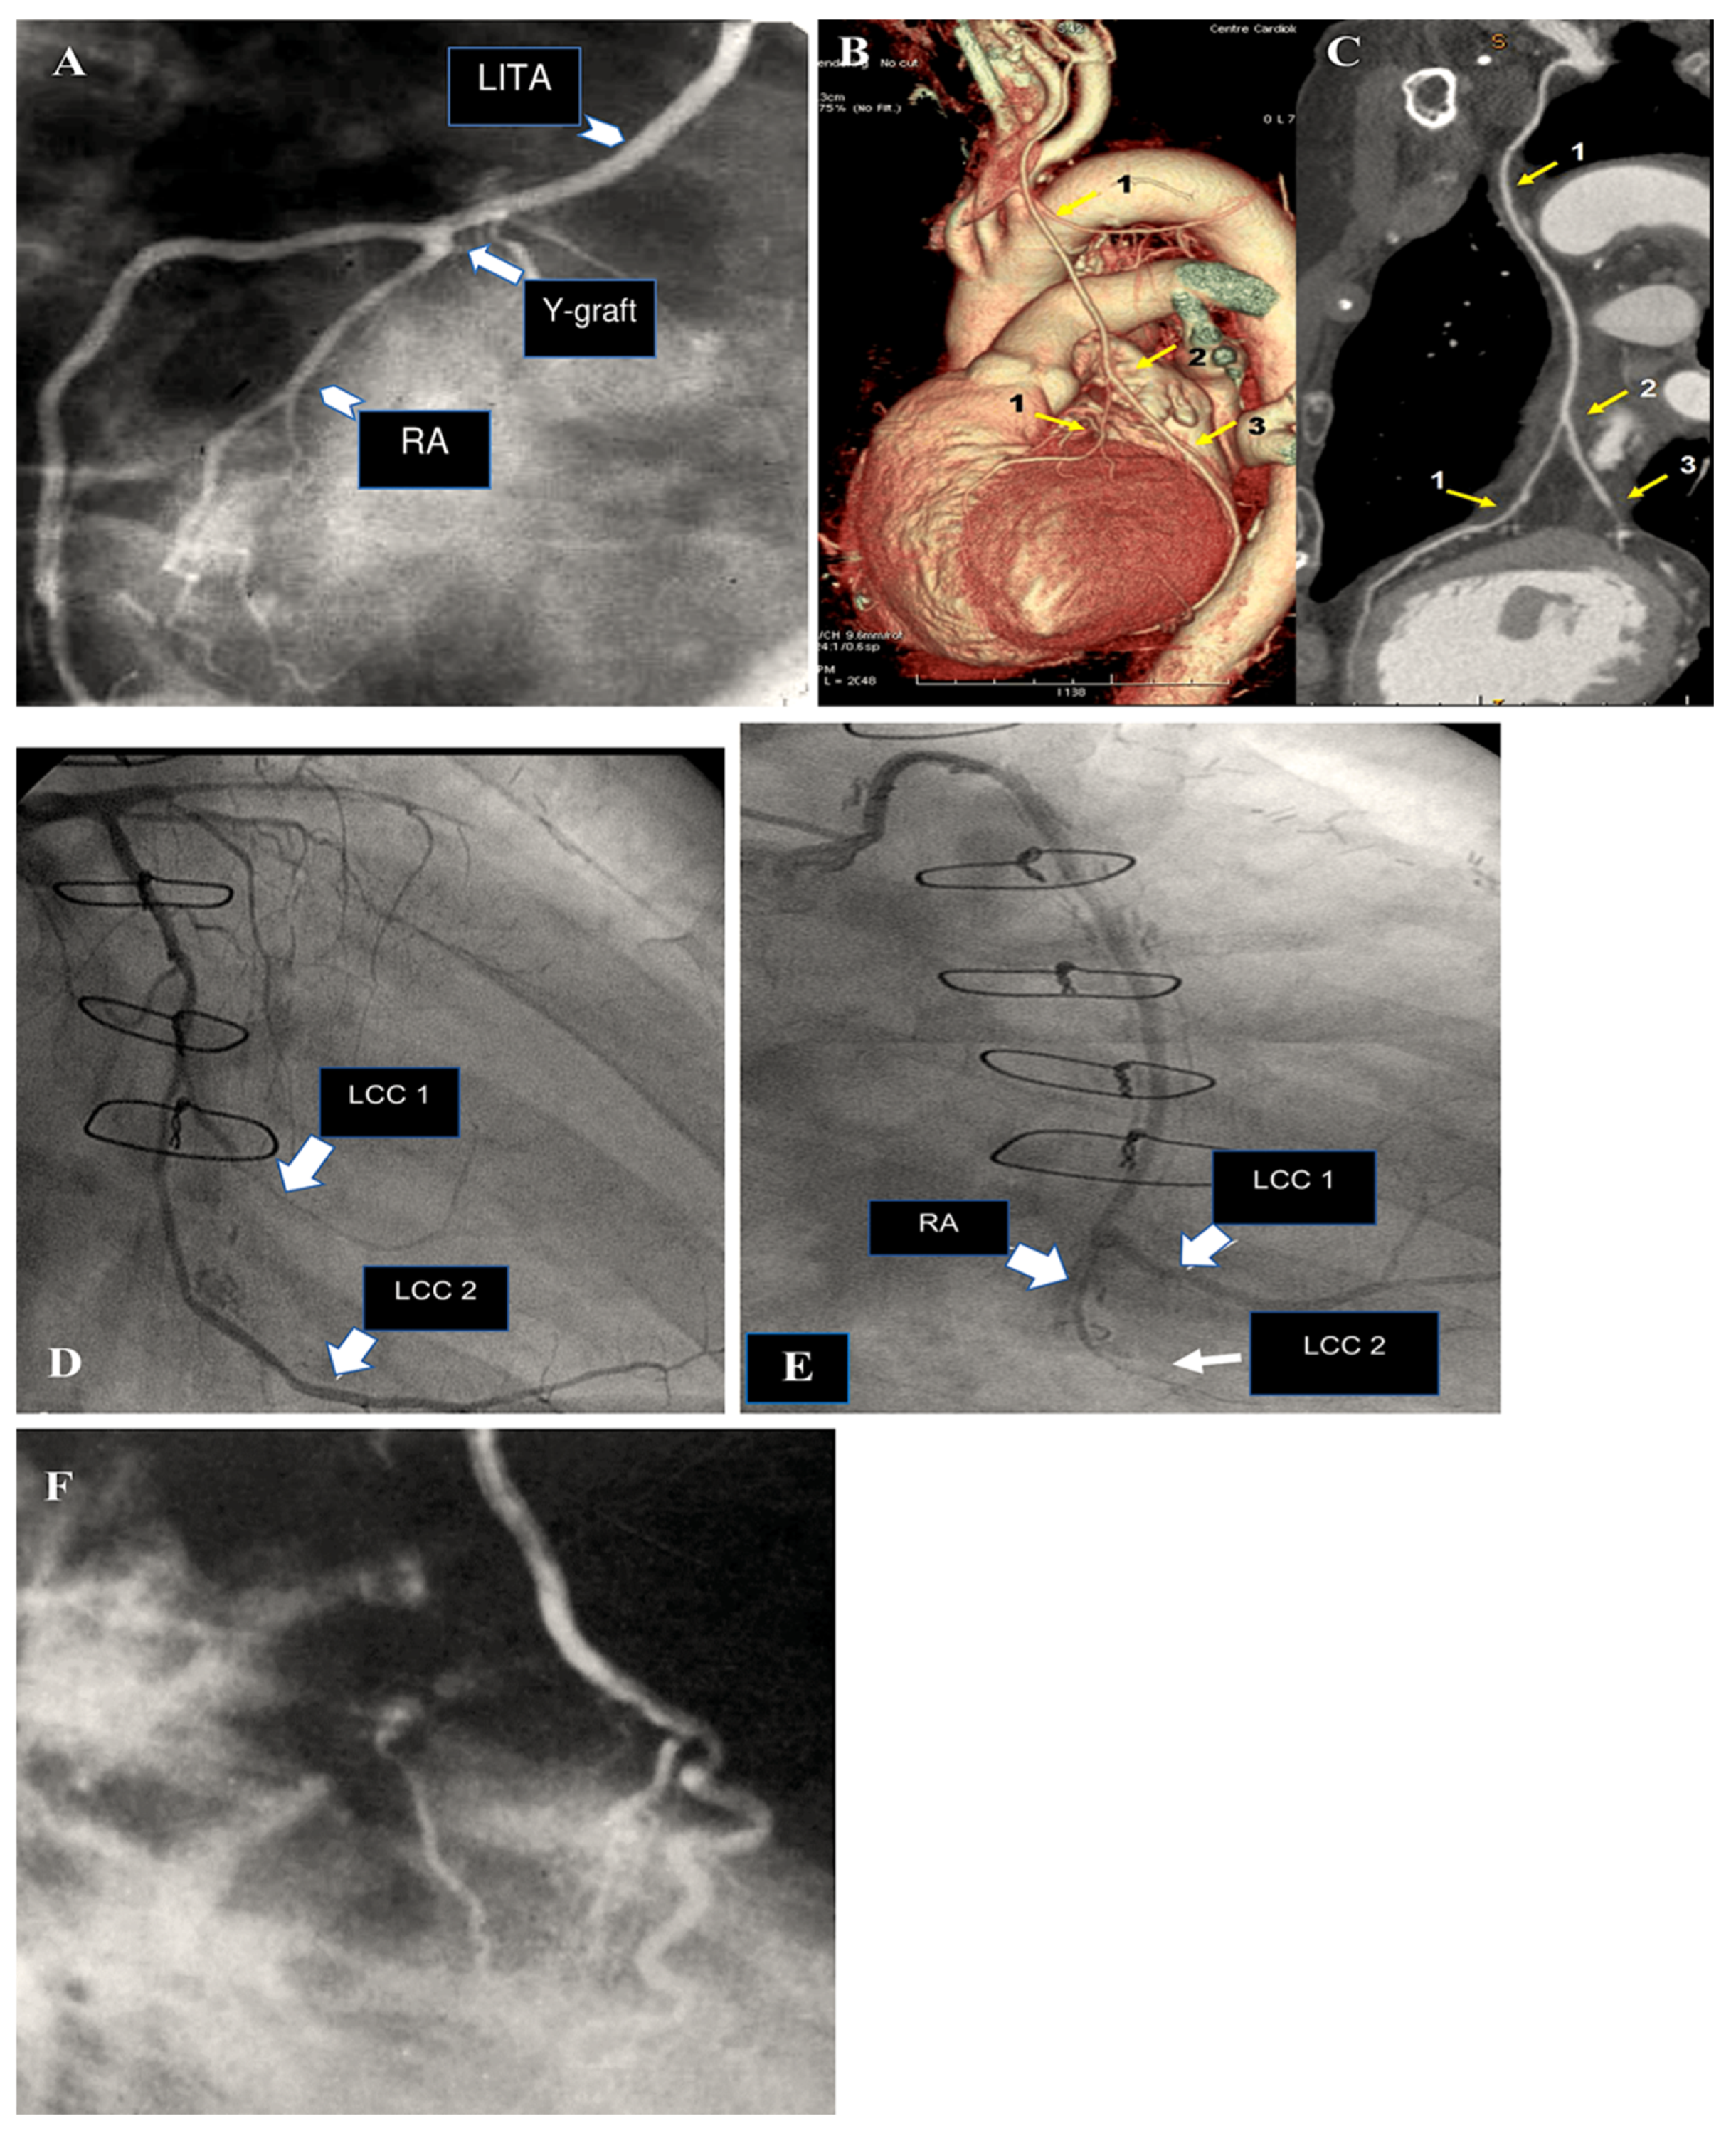

6. The Destiny of Radial Artery Grafts

Determinants of RA Patency

- Goube, P.; Hammoudi, N.; Pagny, J.Y.; Boutekadjirt, R.; Toledano, D.; Achouh, P.; Acar, C. Radial artery graft stenosis treated by percutaneous intervention. Eur. J. Cardiothorac. Surg. 2010, 37, 697–703. [Google Scholar] [CrossRef] [PubMed]